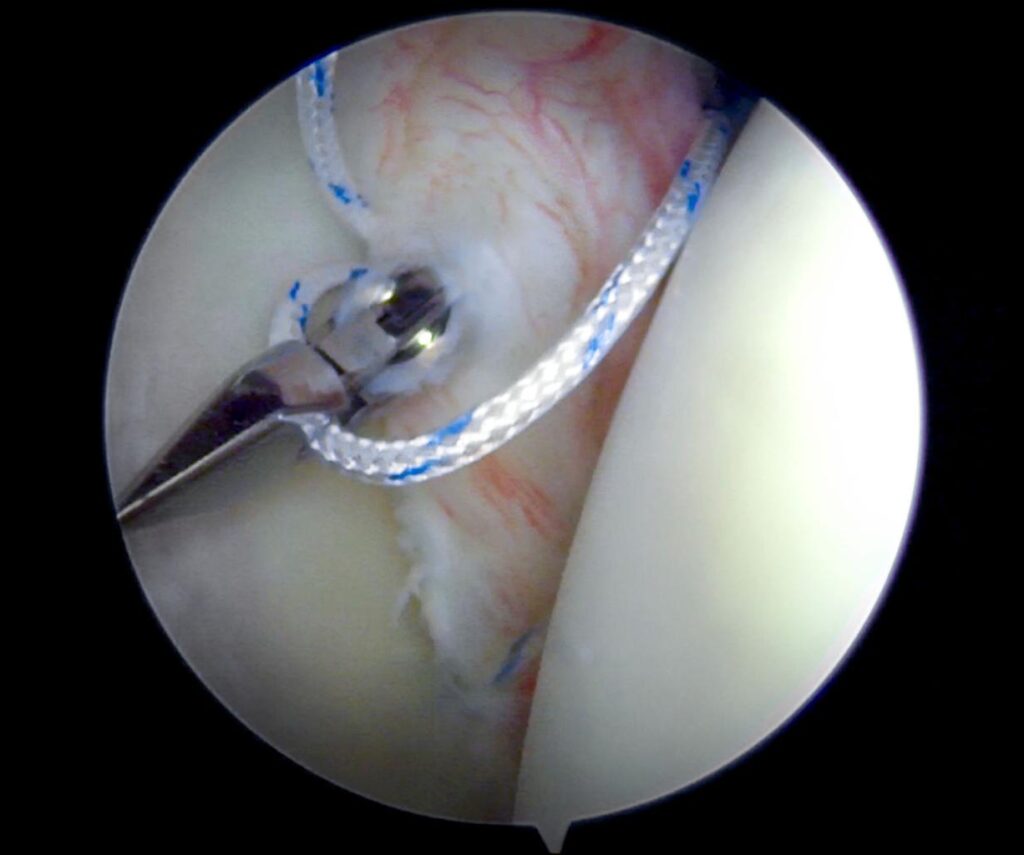

• For recurrent dislocation, keyhole arthroscopic surgery is often the best treatment.

The procedure involves:

• Repairing the torn labrum (Bankart repair)

• Tightening the shoulder capsule

• Fixing instability using suture anchors